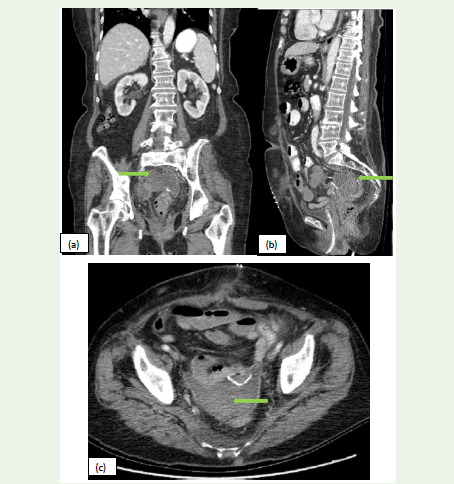

Figure 1: (a, b,c):Sagittal, Axial, and Coronal CT images of a 55-year-old

female patient presented with c/o abdominal pain. CT scan of the abdomen

and pelvis without contrast shows diffuse wall thickening of the stomach/

proximal jejunum with a defect at the site of anastomosis and extra-luminal

air loculi (red arrow) and fat stranding in the left upper abdomen (yellow

arrow), suggestive of anastomotic leak.